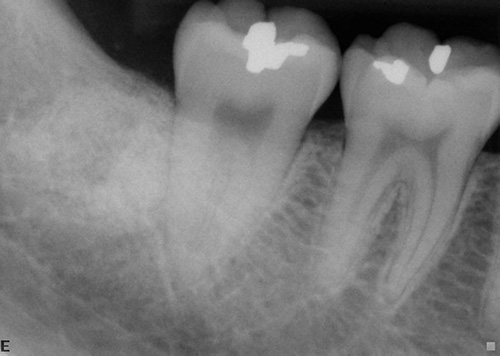

Orthodontic Treatment X-ray - After